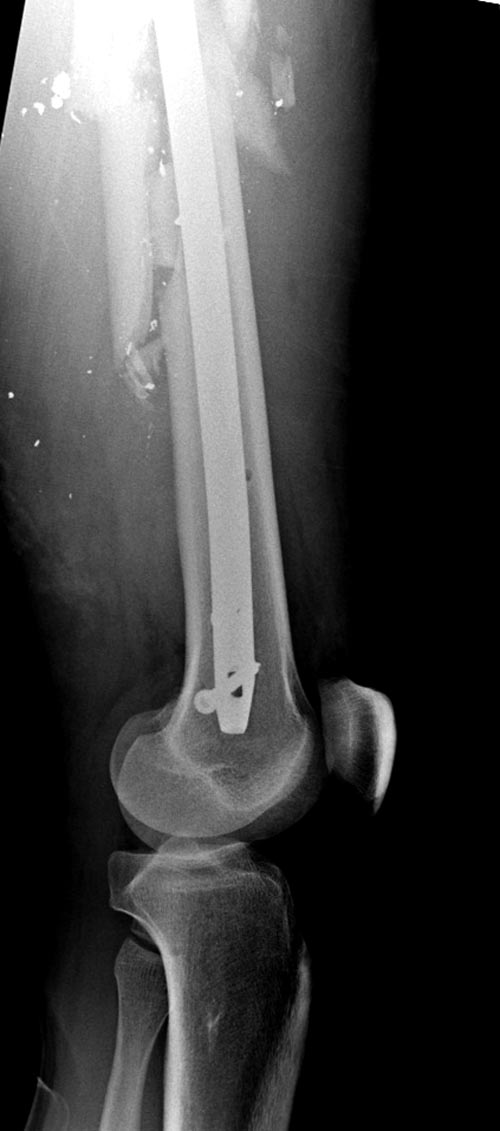

ДТП, открытый оскольчатый перелом левого бедра со смещением Наложение АВФ на левое бедро 31.03.12 *Перемонтаж АВФ на левом бедре 20.04.12 *Снятие АВФ 25.07.12 Перелом регенерата 28.07.12 -Повторное наложение АВФ. В последующем с образованием функционирующего свища. *1.11.12 Демонтаж АВФ с левого бедра, удаление отломка стержня *20.11.12 БИОС левого бедренной кости *21.06.13 Удаление стержня из левого бедра. *8.10.13 Секвестрнекрэктомия левой бедренной кости ,коллапано-мышечная пластика секвестральной полости *21.01.14 Фистулосеквестрнекрэктомия левого бедра с коллапанопластикой

На снимках осложнение огнестрельного перелома бедра поздней инфекцией. 7 лет назад оперирован: правое бедро, сперва на ExFix, затем заменен на гвоздь, а левая - гвоздь при поступлении.

Беспокойство проявил недавно, по поводу жалоб на боли сделано МРТ и дренирование абсцесса терапевтами. Мы удалили гвоздь, сделали I&D, рассверливание канала, и ввели гвоздь с антибиотиком. Для гвоздя использовали стерильную трубку-форму, а антибиотик по 1.0 Tobramycin c Vancomycin.

Рекомендуется: антибиотический гвоздь на цементе. Нагрузку можно разрешить сразу, перелом сросся давно!